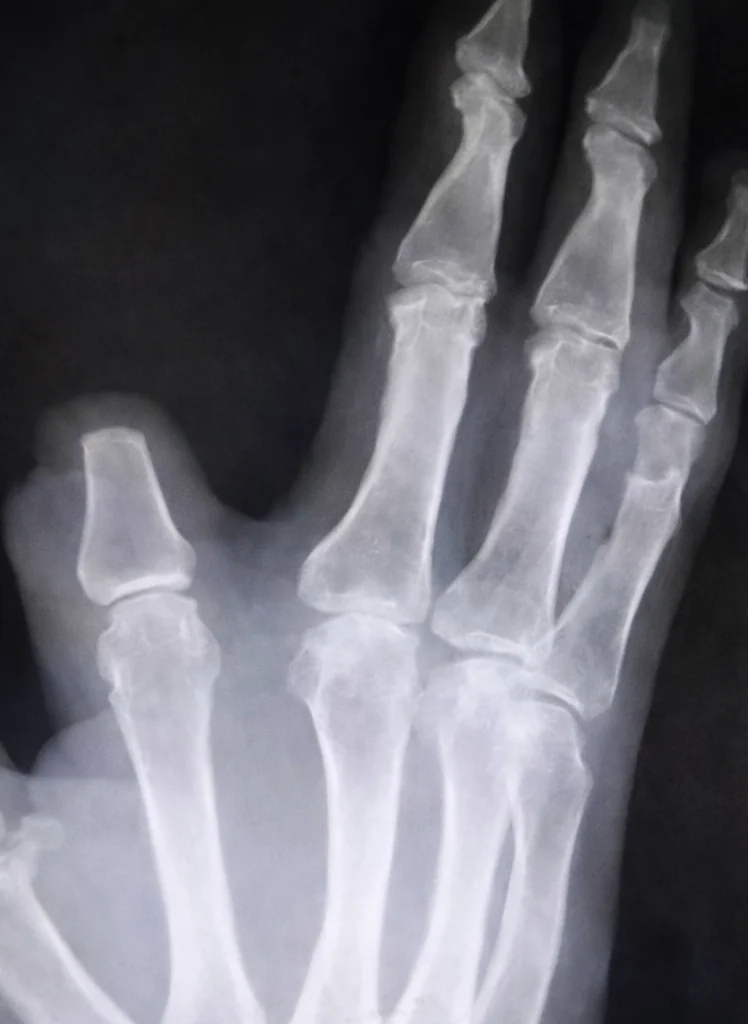

Um agricultor chinês de 60 anos, identificado apenas como Zhang, amputou parte do próprio dedo indicador após ser picado por uma cobra na zona rural de Shangyu, na província de Zhejiang. O incidente, ocorrido recentemente, foi motivado pelo temor de que o veneno da serpente se espalhasse pelo corpo. Após o ato, o homem percorreu cerca de 80 quilômetros até um hospital em Hangzhou em busca de socorro especializado.

Ao ser avaliado pela equipe médica, Zhang descobriu que a serpente responsável pelo ataque não correspondia à espécie altamente perigosa que ele acreditava ter identificado. O paciente não exibia sinais clínicos típicos de envenenamento grave, como sangramento, dores de cabeça intensas ou dificuldades respiratórias. De acordo com os especialistas, o veneno da víbora em questão possui um efeito mínimo e é considerado muito fraco para causar danos severos a seres humanos.

O médico que prestou o atendimento, Yuan Chengda, lamentou a decisão precipitada do agricultor, ressaltando que o procedimento de amputação foi desnecessário. “Não era necessário cortar. Aquela cobra não é tão tóxica”, afirmou o profissional. Devido ao intervalo de tempo entre o incidente e a chegada à unidade de saúde, o pedaço do dedo removido não pôde ser reimplantado.